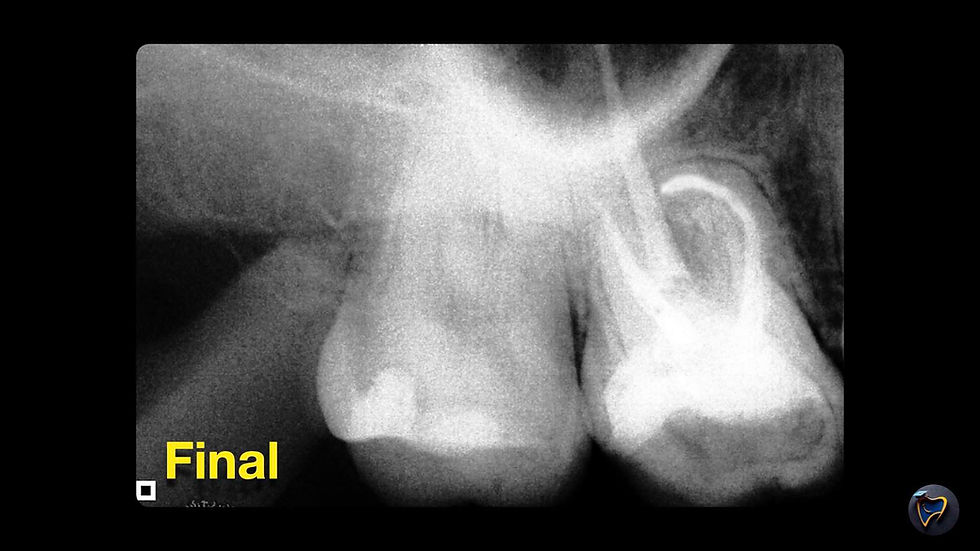

Nas imagens acima (arraste para o lado), podemos observar uma curvatura extrema na raiz mésio-vestibular. A análise radiográfica revela uma curvatura acentuada com um raio de curvatura pequeno, o que requer o uso de uma lima com alta resistência à fadiga cíclica.

Portanto, para essa raiz, a escolha mais indicada é o uso da NeoFile nos canais vestibulares. Já para o canal palatino, foram utilizadas as limas Race Evo.

Radiografia Final: Uma radiografia periapical é tirada após a obturação para verificar a qualidade do selamento dos canais e a adequação do tratamento.